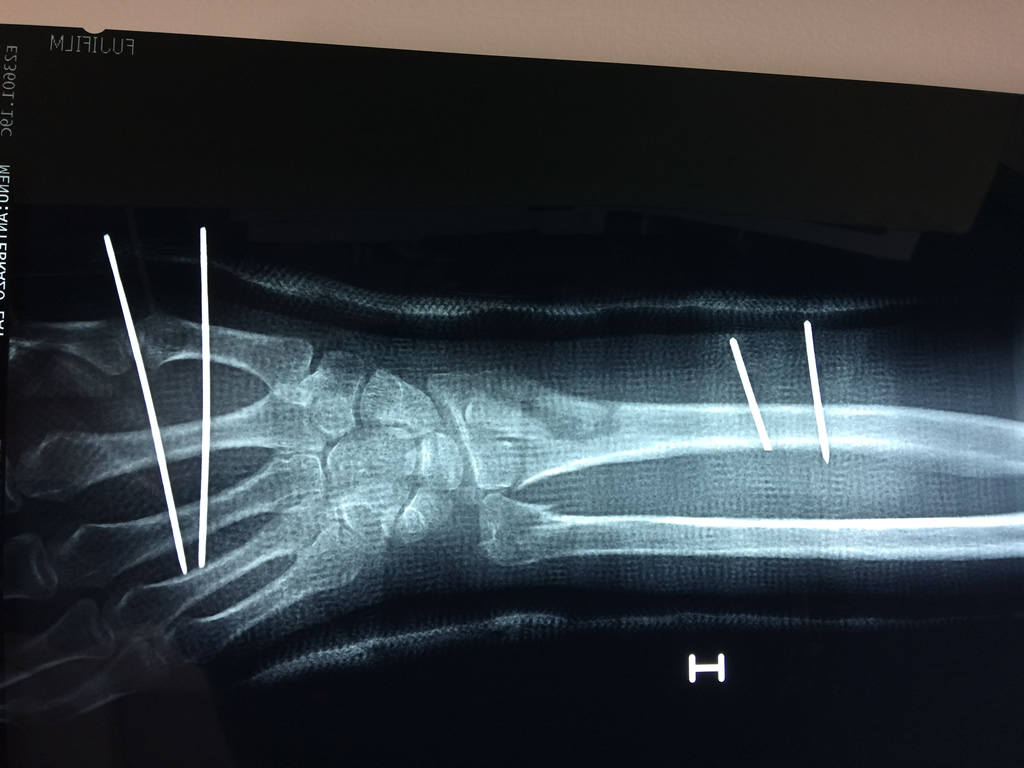

Cirugías de Codo - Cirugías de Muñecas y Manos

Los procedimientos más comunes en cirugía de la mano son aquellos destinados a reparar traumatismos, incluyendo lesiones de tendones, nervios, vasos sanguíneos, y articulaciones; huesos fracturados; y quemaduras, cortes, y otros daños de la piel.